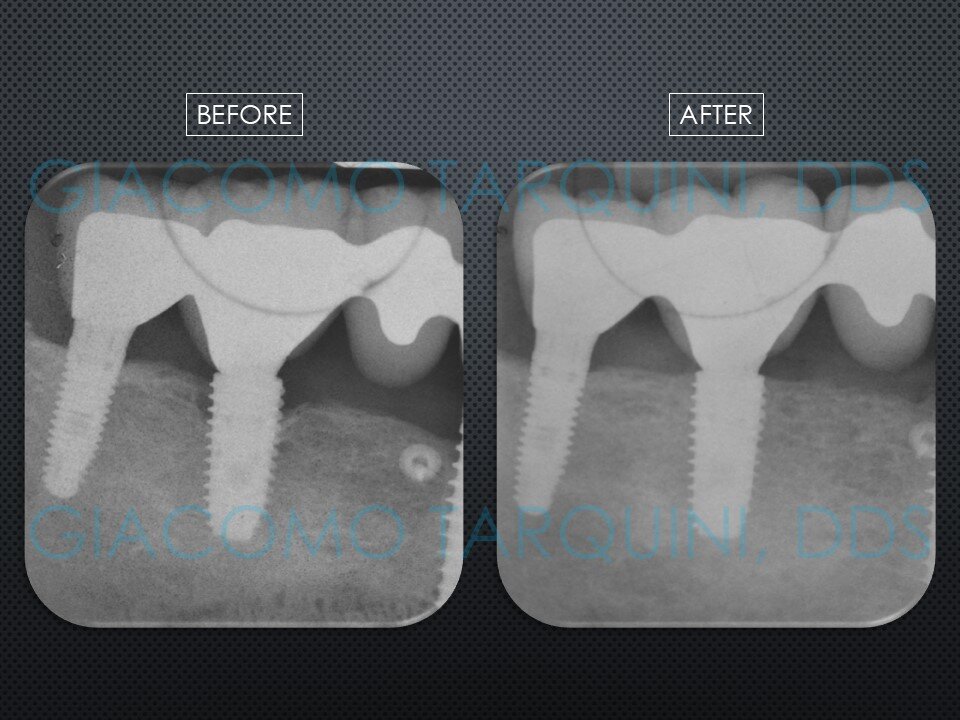

- Rientro chirurgico e follow-up radiografico per valutare il grado di rigenerazione ossea ottenuta

CASO CLINICO

Il caso clinico illustra il trattamento chirurgico-rigenerativo di un impianto endosseo affetto da peri-implantite effettuato secondo il protocollo «PIEZOCLEAN by Dr. Giacomo Tarquini»

Il protocollo chirurgico presentato consente di decontaminare sia la superficie esterna che la superficie interna dell'impianto con soddisfacente predicibilità senza alterarne la macro e microgeometria, rendendo cosi' possibile un nuovo processo di "re-osseointegration".